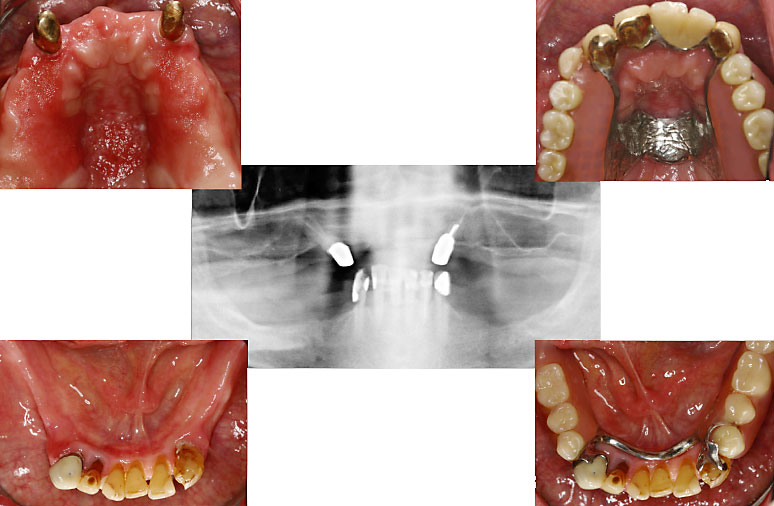

Fall: festsitzender Zahnersatz im Ober- und Unterkiefer